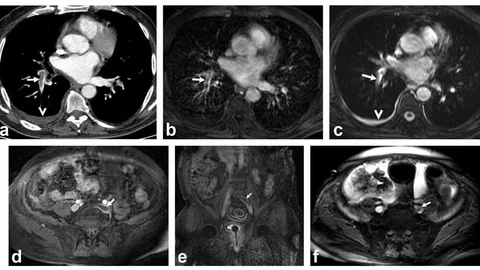

Denizli | 6 1…567…1396/139 Tavas'ta Servis Aracı Kaza Yaptı Buldan'da Kar Yağışı Etkili Oldu Denizli'de Halk Oyunları Şöleni Denizli Lisesi İçin Yenilenme Projesi Başlatıldı Kadın Fotoğrafçılardan 'Adı Mutluluk' Sergisi Denizli'de Denizli'de TIR Dorsesi Yola Savruldu Denizli'de Koyun 9 Yavru Doğurdu Denizli'de Kadın Su Kuyusuna Düştü Denizli'de İş Adamı Cinkaya Açıklama Yaptı Honaz Belediyesi Araç Filosu Güçlendi Ramazan Coşkusu Buldan Sokaklarında Yaşandı Denizli'de Kuruyemiş Fabrikasında Yangın Çıktı Merkezefendi'de Ramazan Bereketi Tavas Baklavası Dünya Pazarına Açılıyor Denizli'de Kaçak Kazı Tehlikesi Denizli'de Kaçak Kazı Tehlikesi Denizli Kız Yurtlarında Modern Kafeterya Açıldı Çameli İmam Hatip Lisesi'nde İftar Programı Tavas'ta Kamyonet Devrildi, Yaralılar Kurtarıldı Denizli'de Emniyet Kemeri Eğitimi Miniklere Sağlıklı Beslenme Eğitimi Verildi Honaz'da Kadınlara Çiçek Dağıtılacak Kale’de İlk Yardım Eğitimi Seferberliği Anahtar Partisi Denizli'de İftar Yemeği Düzenledi Denizli'de İftar Sofrası Kuruldu Akciğer Pıhtılarında Radyasyonsuz Çözüm Denizli'de Trafik Magandasının Ehliyeti İptal Edildi 1…567…1396/139 Denizli Haber Merkezi • 18 Kasım 2025 04:35 Facebook X WhatsApp 18 Kasım 2025 04:35